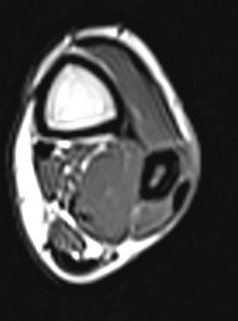

Pilon fracture - Wikipedia, the free encyclopedia

Pilon fracture - Wikipedia, the free encyclopedia from upload.wikimedia.org